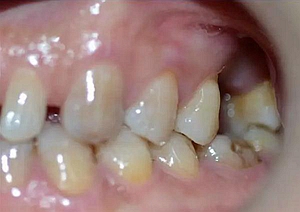

患者:男,37歲。左上后牙確實多年。既往體健,否認麻醉和牙槽外科禁忌。

術(shù)前口內(nèi)照